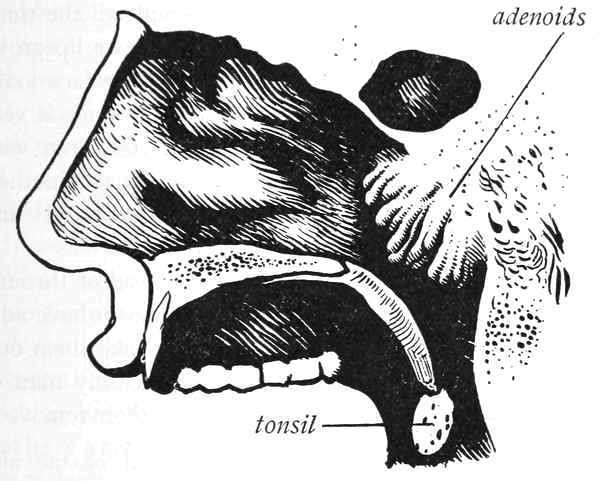

The most common reason for mouth-breathing is the growth of small lumps in the throat just behind the nose. These little lumps are called adenoids. They are not natural, and should be taken out. We do not know why they grow in some children and not in others, but we do know that they should be taken out so that the child can breathe easily through the nose. Large tonsils also cause[50] boys and girls to breathe through the mouth. Tonsils that are large enough to cause the child to breathe through the mouth ought always to be taken out. Large tonsils and adenoids are often found in the same child.

When a child breathes through his mouth all the time, his face takes on a peculiar shape. His upper lip grows long, his lower jaw drops back, and his whole face looks flat. His voice has a peculiar sound, and he finds it very hard to keep up in his classes at school. Children with adenoids and large tonsils are always backward in their school work, and may become deaf if the adenoids and tonsils are not removed.

If you breathe through your mouth instead of through the nose, go to the doctor and let him see if you have adenoids or large tonsils; if you have, let him take them out. You cannot possibly grow into a strong, healthy man or woman if you have adenoids and do not have them removed.